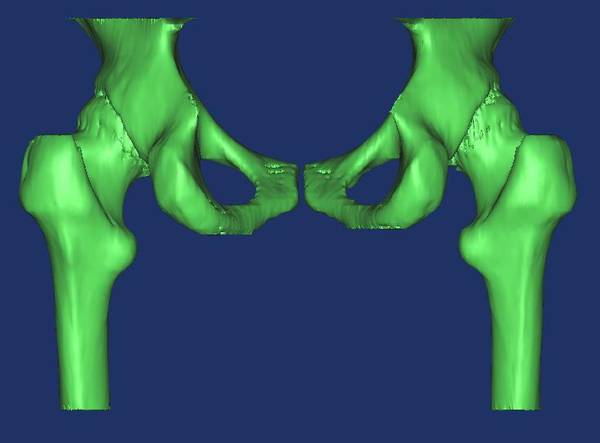

- 全髋关节置换手术中植入的假体多为生产商制造的标准化产品,由于受产品规格限制,使得假体与患者骨的匹配程度较低,术后易出现双下肢不等长的现象,不同程度影响了患者的术后生活质量。假体的松动是全髋关节置换手术术后另一个主要的并发症,也是导致假体关节脱位、返修的主要原因。这除了假体与患者骨的匹配程度较低有关外,还与另外两个因素有关,一是术中临床医师大多数凭着自己的经验决定植入假体的位置和深度以及切除坏死股骨颈的高度,导致假体与股骨有效髓腔的契合度降低,出现术后双肢不等长,假体下沉等现象;二是植入假体后力的传入途径发生了根本的变化,关节应力直接通过假体传到髋关节,而不同于生理关节的应力通过骨小梁从髋关节传到髋关节,造成应力遮挡,使得骨组织被吸收而萎缩,减低其承载能力,改变应力集中点,病人出现术后剧烈疼痛等现象。上述问题的理想化的解决方案,一是 “量体裁衣”、设计、制造在形态学、生物力学、材料力学等方面能最佳适应个体髋关节解剖特点的个体化、定做式人工髋关节;二是实际手术前虚拟、演练植入过程、精确预知植入后的效果。 多排螺旋CT和较高磁场MR等现代医学成像设备对疾病的解剖显示日益精细。计算机技术及现代医学成像技术的显著进步为运用反求工程技术原理及计算机虚拟现实技术应用于术前手术虚拟、植入假体设计制造等提供了现实途径。 本课题运用反求工程技术原理,采用薄层CT扫描数据计算机辅助重建活体髋关节三维CAD模型;基于Billing等定义及立体解析几何原理,计算机辅助、精准、半自动化地分别测量股骨头直径、容积及中心位置、颈干角、髋臼前倾及外展角度、髋臼窝半径等重要解剖参数;应用计算机虚拟现实技术、计算机逼近拟合算法及有限元力学分析等工具,虚拟理想化假体模型,研究其形态学;虚拟假体植入,比较活体髋关节重建模型及假体植入后的力学分布曲线,为人工髋关节置换术前三维可视化、优化手术方案以及研制适合国人体质、高契合度及最佳力学曲线分布的定制髋关节假体等提供技术探讨、实体模型和设计依据。 为此,本组研究分别从以下五个方面展开: (1)探讨一种精准、简便的股骨颈前倾角测量方法及其临床应用及其临床应用;推导出股骨颈前倾角公式,采用公式法计算右侧前倾角为17.3251°±1.1345°,传统法测量16.853°±7.631°; (2)基于以上方法和测量过程,系统测量左右侧髋臼前倾角等解剖学参数,为人工髋关节置换手术及个性化定制假体设计提供解剖学基础并初步探讨临床应用软件设计与开发; (3)髋关节三维可视化和形态学研究。采用髋关节螺旋CT数据,半自动分割髋臼窝、股骨头、股骨颈及股骨干,体素重建的方法对髋关节及股骨同时进行三维重建,从不同的角度观察髋关节三维立体及其周围重要结果毗邻关系,并在模型上进行三维解剖学测量,探讨其临床应用;为髋关节手术治疗、微创外科、立体定向、导航系统及虚拟假体设计提供三维可视化模型; (4)构建正常成年人股骨三维有限元模型。模型导入ANSYS 10.0软件后进行体网格划分,并再导入Materialise软件进行模型材料属性赋值,在ABAQUS软件定义边界条件,模拟直接暴力作用股骨干横界面生物力学研究,垂直水平面加载500N载荷,观察载荷后关节及股骨的应力曲线分布,提示股骨干以其内侧中下1/3交界处的应力最大,应力值分别为29.0Mpa,从而为假体材料和植入后的研究提供有限元力学分析基础。 (5)模拟具有理想形态学的人工髋关节植入。根据所测得的相关参数,设计理想形态学的假体模型,导入3D功能模块,虚拟三度空间精确调整假体植入体中的位置。在计算机中成功的实现个性定制假体等手术,并可预见和评估手术的结果,从而制定出最优的手术方案。患者所需假体和髋臼杯的型号将以报告的形式输出,为提高手术成功率及延长假体植入的寿命提供了一条新的、精确合理的途径。

- 目的:为研制适合国人体质、高契合度及最佳力学曲线分布的定制髋关节假体及优化手术方案等提供技术探讨、实体模型和设计依据。方法:1.反求工程技术原理计算机重构30例健康成人在体髋关节三维模型; 2.根据Billing定义及解析几何学原理推导出以定义的关键点坐标值为自变量的股骨颈前倾角计算公式,自动计算前倾角等参数; 3.计算机辅助拟合髋臼窝、股骨头、股骨上段髓腔等形态; 4.虚拟假体植入,分离骨皮质和髓腔,虚拟生理不同受力情境,有限元力学分析软件分析其力线分布; 5.根据上述结果筛选形态学、力学分布最优化假体,优化手术方案; 结果:1.推导出股骨颈前倾角公式,测量重要形态学参数; 2.重建出了髋关节三维可视化模型并可任意、实时旋转观察; 3.股骨三维有限元模型以内侧中下1/3交界处的应力最大,应力值为29.0MPa; 4.计算机虚拟实现个性定制假体等手术,并可预见和评估手术的结果、最优化手术方案。患者所需假体和髋臼杯的型号以文本报告的形式输出。 结论:上述公式、三维有限元模型及假体设计、虚拟植入等可应用于定制理想髋关节假体设计及优化手术方案。